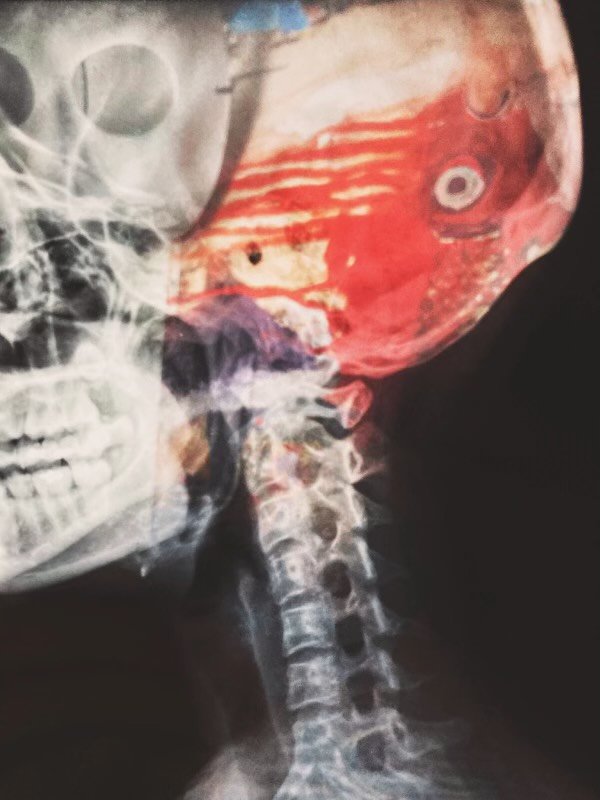

i am suddenly a living replica of my father // stagnant, muttering terminology i hardly can google // a small recorder catches the syllables // falling off his speech // his right hemispheres contort // on radiology monitors // dissipate and reappear // like our waning arguments in the dead of night // “who pays for your dinner” // “who is fulfilling your filial dreams” // optical illusions, if you stare long // enough you’ll find yourself morphing // without knowing how to readjust to the world apart from distraction // like him, disease salutes me // knees permanently burrowed in my chest // this is where i enter the underpass // an email that read ______      // how could you distract me from my friends, izzy writes // how could you be cremated // in your own bandages, unbinding // immersed in your ambition not even half // invested in mine // how could you leave me // without a ribbon to my name // dad told me to mind my allergies // distance myself from idiopathism // but i was splintered in hindsight from // other relationships // by avoiding introverted tendencies // papa and i // become them // pity was the skin // sheathing me when my arteries bulged // she curtailed my speed // then catapulted off the threshold // laid bare on my psyche // with built in fractures // i sacrificed a lamb, or two // or maybe a limb // they were insomniac creatures // no easy blessings // unlike my father, i am no cure // i pray that claritin picks apart this landmine // bloodclots stifled by // “sorry, i take that back” // and calls left unanswered // my skin tightens across my thighs and hacks from obsession // little by little // this body has been borrowed // and blued by self-absorption // no IV tubes can drain // sterile winds whir above me // my cerebrum uploaded to his HP laptop // i can’t study // dad taps my shoulder twice // relentless to answer // for himself // where i’ve been // he asks why my face has lost its red // and why i’ve been so difficult to read // i tell him i’ve hijacked my own diagnosis // not realizing all i succumb // until the only condition left // a patience, disintegrated // we are always immune // to each herring, except // for when we straighten our backs // against the magnetic resonance // imaging without         // never there the last time // we checked